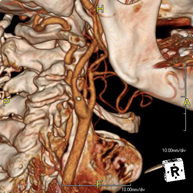

- Angio – TC Troncos Supraaórticos

Prueba radiológica que consiste en obtener imágenes de las arterias carótidas del cuello de alta definición anatómica mediante el empleo de un equipo de TC (Tomografía Computarizada) y la inyección de contraste intravenoso. Posteriormente, las imágenes son reconstruidas en tres dimensiones (3D). Indicaciones: accidente vascular cerebral agudo, accidente vascular transitorio, soplo carotídeo.

- Angio-TC-Troncos Supraaórticos